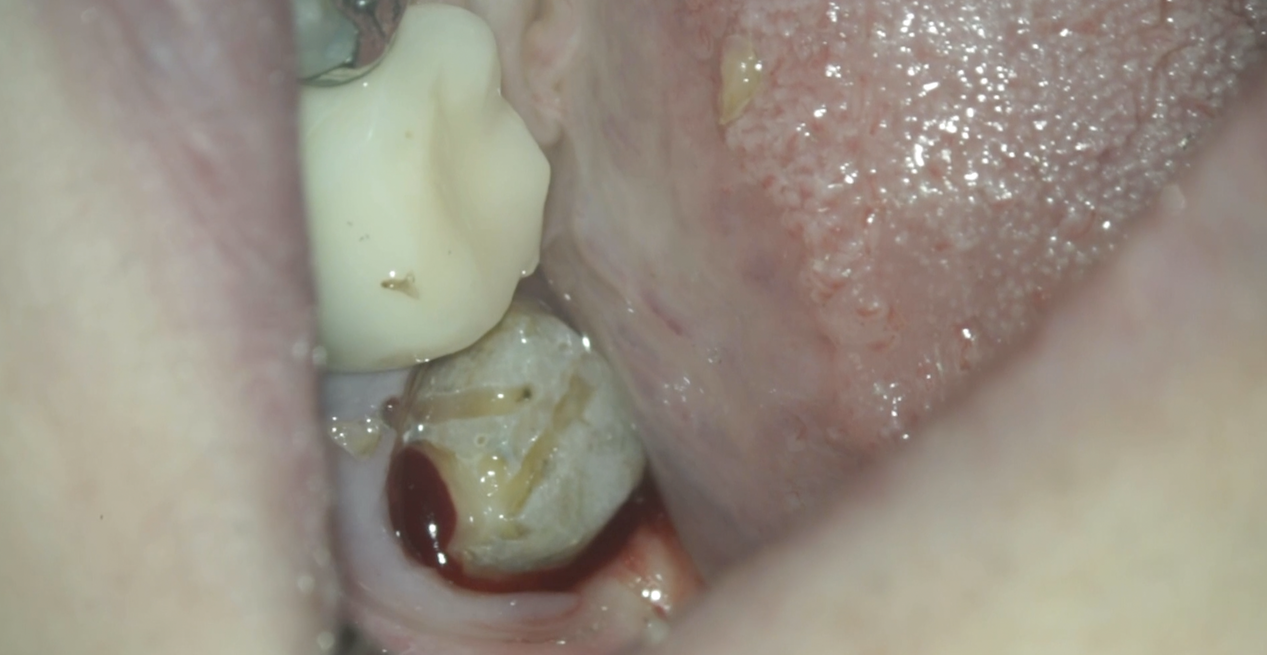

#18 RCT(2025.12.4)

除冠し当該部位を削ると…

既に虫歯が縁下にまで及んでいた。

これが主訴(左下奥がうずいたり、歯磨きをするときに痛い…食事をするときにも痛い。痛みが強くなると顎まで痛みが出ることがある…)の原因だったのだろう。

ではそれになぜ気付けたか?だが、

明らかにCBCTの存在がなければこの存在に気づけなかっただろう。